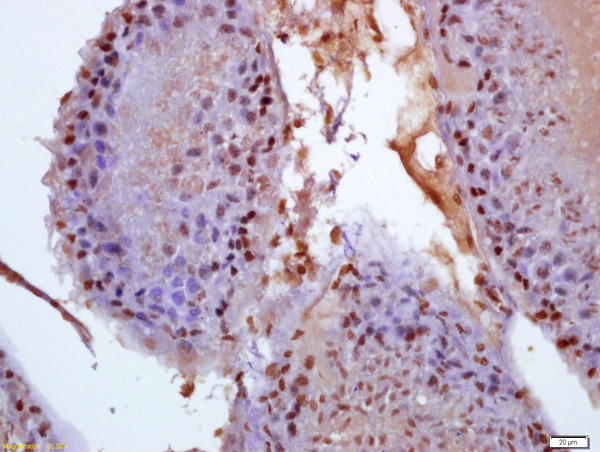

- Main image

- Experimental details

- Formalin-fixed and paraffin embedded rat testis labeled with Anti-phospho-BCAR1(Tyr410)Polyclonal Antibody, Unconjugated (bs-6224R) at 1:200 followed by conjugation to the secondary antibody and DAB staining

- Sample type

- Other comments

- Testis